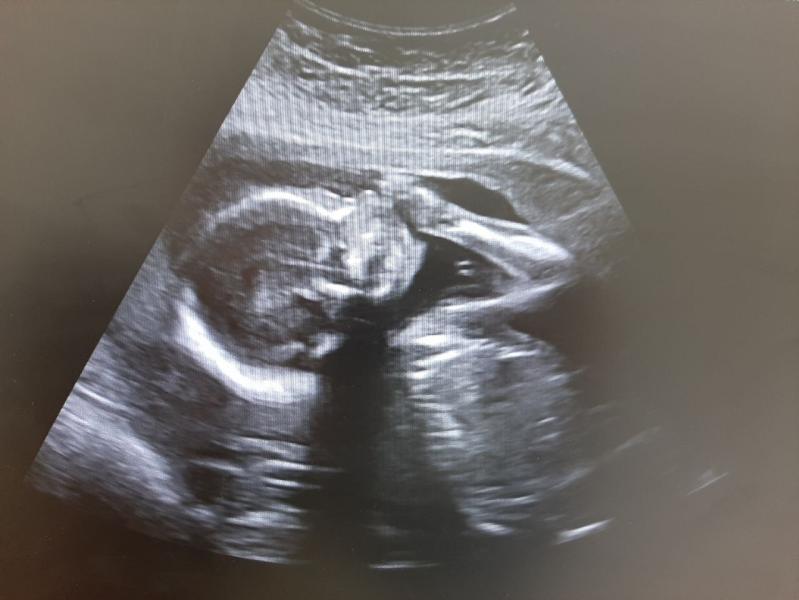

Ну вот и мы "дожили" до второго скрининга. В свои 20 недель мы весим 330 гр.. Сказать что я рада, ничего не сказать. Если учитывать то, что я очень переживательная! У сыночка все хорошо, маме куча анализов. Возраст говорит "привет". Вот думаю, носить в 25 легче чем в 35?